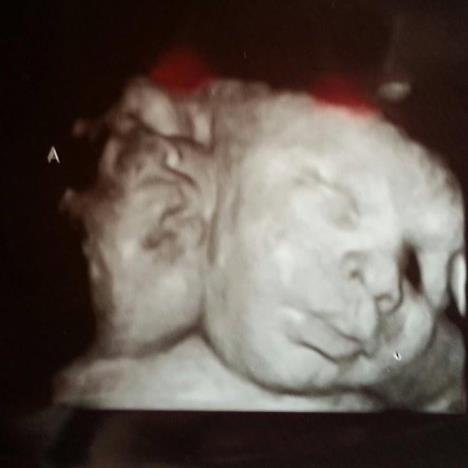

"Bebe su za sad dobro", objavio je njihov otac Majkl na Fejsbuk stranici "Hamby twins". Dečaci su na porođaju bile teški četiri kilograma i 100 grama. Porođaj je protekao bez većih komplikacija. Posle rođenja ustanovljen je manji zdravstveni problem na srcu, tačnije na desnoj strani, ali su lekari uspešno sanirali problem. Ovi blizanci su rođeni sa dve glave i jednim telom, spaja ih jedno srce i zajednički krvni sistem, pa nikad neće moći da se razdvoje. Njihovo stanje se naziva dicephalic parapagus.

Dečaci iz Atlante su pobedili sve prognoze, iako su slučajevi spojenih bliznakinja tri puta češći, Eli i Asa su "rešili" da budu pravi izuzetak. Pored toga što dele ruke, noge, srce, jetru, oni imaju tri bubrega, svaka beba koristi svoj i trećinu zajedničkog bubrega.